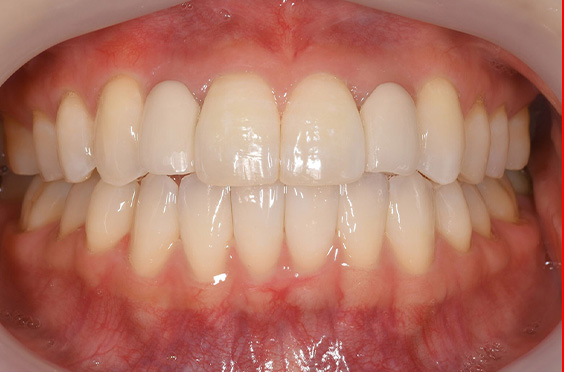

- 症例1

治療期間 4カ月

治療費 23.1万円(月額1,925円~)

※上顎前歯部、下顎前歯部の叢生をマウスピース型矯正装置で改善したケース。矯正治療上のリスクとして、治療中の虫歯、歯根吸収、歯肉炎 ・歯周炎の発生などが考えられる。